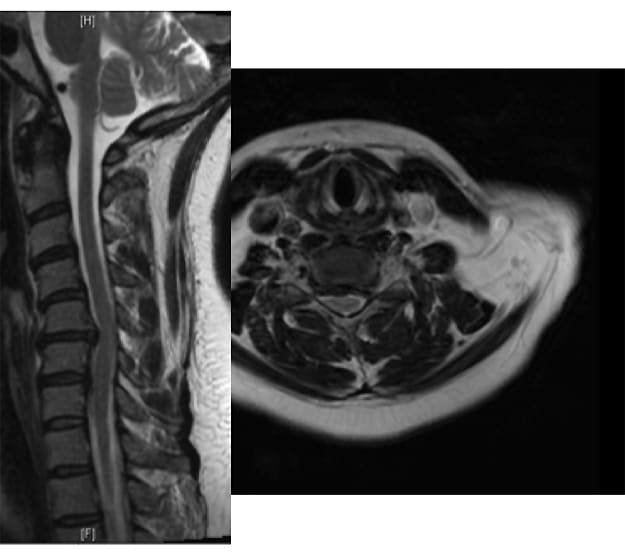

The intervertebral disc is a shock absorber that is located between the bony vertebral bodies in the neck, upper and lower back. It is composed of a firm outer layer and a gelatinous inner layer. When the outer layer is injured, the inner layer is extruded and can result in a pinched nerve. While common in professional football players, these injuries are not limited to contact sports as Major League Baseball players such as Nick Markakis and Prince Fielder have all been diagnosed with a herniated disc in their neck.

Most commonly, a herniated disc pinches a nerve after it has branched off of the spinal cord, and the injury results in shooting pain that starts in the neck and extends down one arm. In severe cases, this can be associated with arm numbness and weakness. While all athletes who experience these symptoms should see a medical professional, rest and anti-inflammatory medication will alleviate these symptoms in the vast majority of patients; however complete resolution of symptoms can take weeks to months. Strenuous athletic activity in the setting of ongoing symptoms is not recommended as this may worsen the symptoms.

If anti-inflammatory medication and rest does not relieve an athlete’s symptoms, surgical intervention is extremely effective at addressing an athletes arm pain. A surgeon can do this from the front of the neck by removing the entire intervertebraldisc and stimulating the two vertebral bodies to fuse together. While this is the most tried and true method, athletes should not return to play until the bones have fused together, and this often takes between 6-12 months. Furthermore, if the bones do not completely fuse together, additional surgery is needed prior to returning to most athletic activity. Conversely, in select cases, surgeons may be able to remove only the extruded piece of disc from the back of the patient’s neck, and if this is possible, the athlete may be able to return to athletic activity substantially faster. Regardless of the surgical treatment, patients should not return to sporting activity until they have regained complete range of cervical motion and strength in their neck and arms.

Rarely, herniated discs in the neck can lead to compression on the spinal cord. This often leads to difficulty with balance, numbness and tingling in the hands, weakness is the arms and legs and rarely difficulty controlling one’s bowels and bladder. If any of these symptoms are present, athletes should seek immediate medical care, as prompt surgical intervention may be needed.